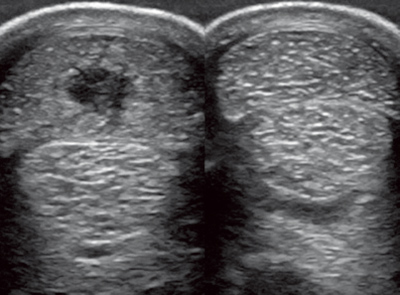

上圖為受傷肌腱的B超顯示,圖右為正常對(duì)比??梢妶D左位于最上方的指淺屈肌腱體積變大(腫脹),中間出現(xiàn)深色區(qū)域(損傷)。B超檢查在治療筋腱軟組織損傷中尤為重要,在整個(gè)治療過(guò)程中,B超可以探查出病變部位的受損情況和恢復(fù)狀況,獸醫(yī)會(huì)根據(jù)B超探查的結(jié)果,制定下一步的治療和恢復(fù)計(jì)劃。